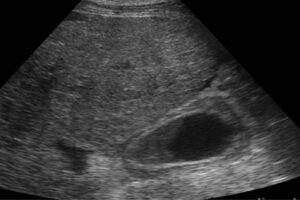

Buenas noticias pues un equipo de investigadoras e investigadores mexicanos han identificado marcadores biológicos que ayudan a detectar cambios o anormalidades antes de que haya síntomas de enfermedades del hígado, particularmente de cirrosis y de hígado graso.

Con diferentes tejidos (sano, con fibrosis, cirrosis o cáncer) evaluaron cómo se expresan los marcadores tempranos o proteínas en hígados sanos y enfermos.

Al haber daños al hígado -como infecciones por virus de hepatitis B o C; consumo de drogas tóxicas, de alcohol por tiempo prolongado; sobrepeso u obesidad- inicia una condición de inflamación en la que los hepatocitos (células principales del hígado) comienzan a morir, y otras llamadas estelares producen cicatrices y más colágena de la habitual.